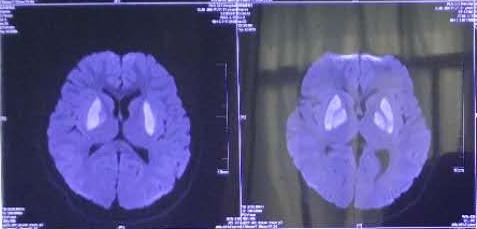

▲ 患者郭某中毒后头颅MRI表现提示基底节区对称性异常信号